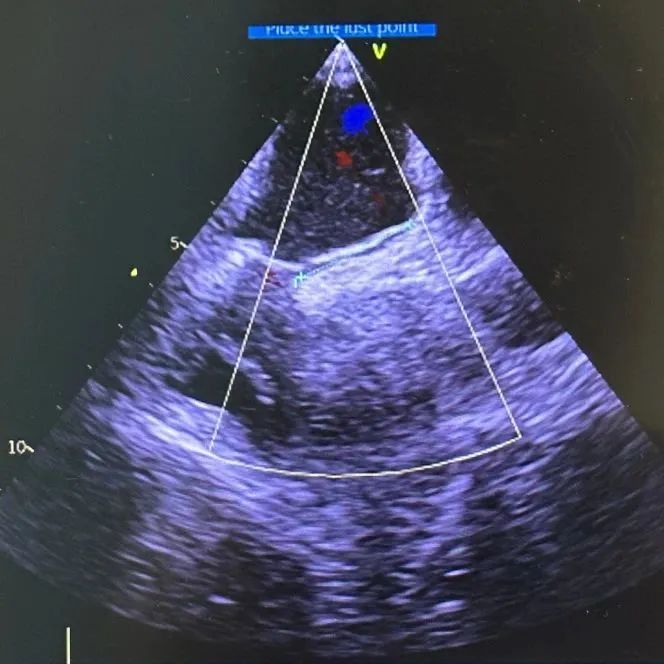

充分术前准备后,耿召华教授、超声科谭开彬教授同台为童爷爷开展手术。

术中,超声探头进入食管,从心脏后方向前近距离探查,进一步发现该卵圆孔未闭为复杂型,手术难较大。其腔道较长,约 24 毫米(一般为 4-18 毫米),且因相邻结构特殊,血液更易反流。